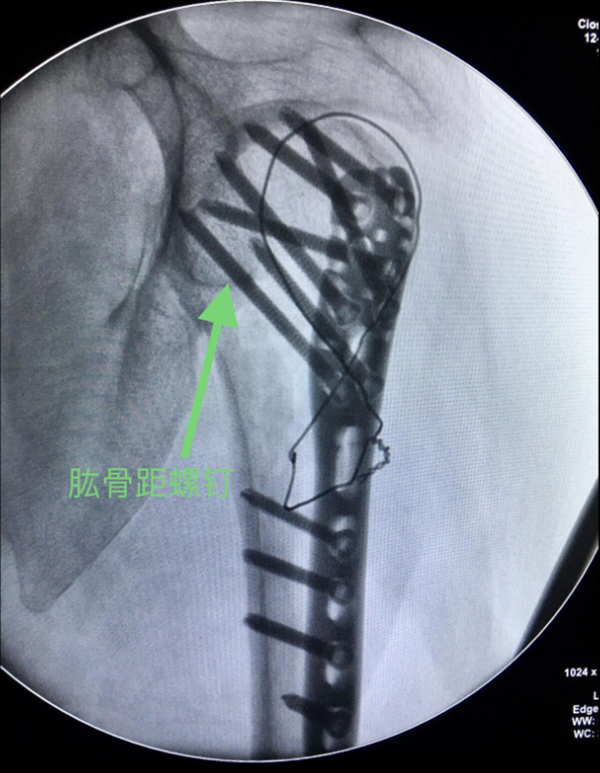

(5)注意肱骨距内侧支撑复位肱骨距,如果内侧皮质支撑结构破坏广泛,可采用髓腔内结构性植骨以重建内侧支撑。如内侧皮质结构尚完整,但出现了内侧的阴性支撑,则需要使用肱骨距螺钉斜跨干骺端与后内侧皮质以行支撑。

图13 肱骨距螺钉固定

2、注意肱骨距的修复与重建,肱骨头骨折块复位不佳存在内翻移位或肱骨距骨缺损,肱骨没有很好地重建内侧的支撑,导致继发性的复位丢失或内固定断裂。可以采用髓腔内结构性植骨以重建内侧支撑。如果内侧皮质结构尚完整,可以使用肱骨距螺钉斜跨干端与后内侧皮质以行支撑。